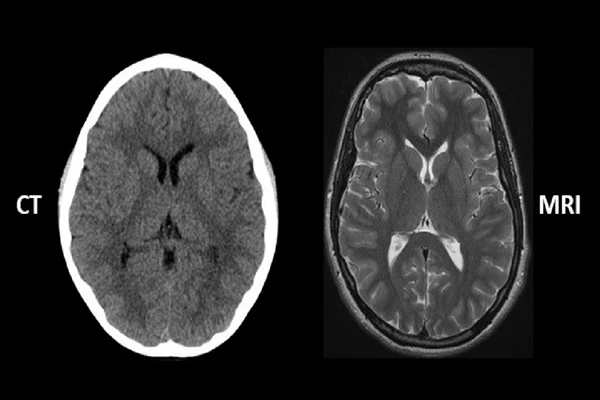

CT vs. MRI: A Detailed Comparison for Technologists

An in-depth comparison of the physics, speed, cost, and clinical applications for each modality.

An Introduction to Computed Tomography (CT)

Learn how CT scanners use X-rays and computer processing to create detailed cross-sectional images.

The Principles of Magnetic Resonance Imaging (MRI)

Explore how MRI uses powerful magnets and radio waves to generate sophisticated images of soft tissues.